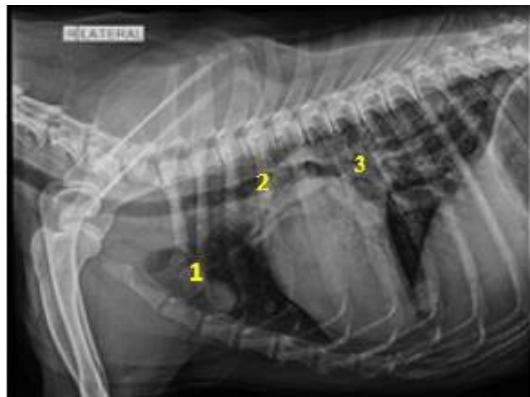

Lekshmi S.L et al. Evaluation of Radiographically Evident Cardio-Pulmonary, Metastatic and Paraneoplastic Changes in Thorax Associated with Superficial and Mammary Neoplasms in Dogsa